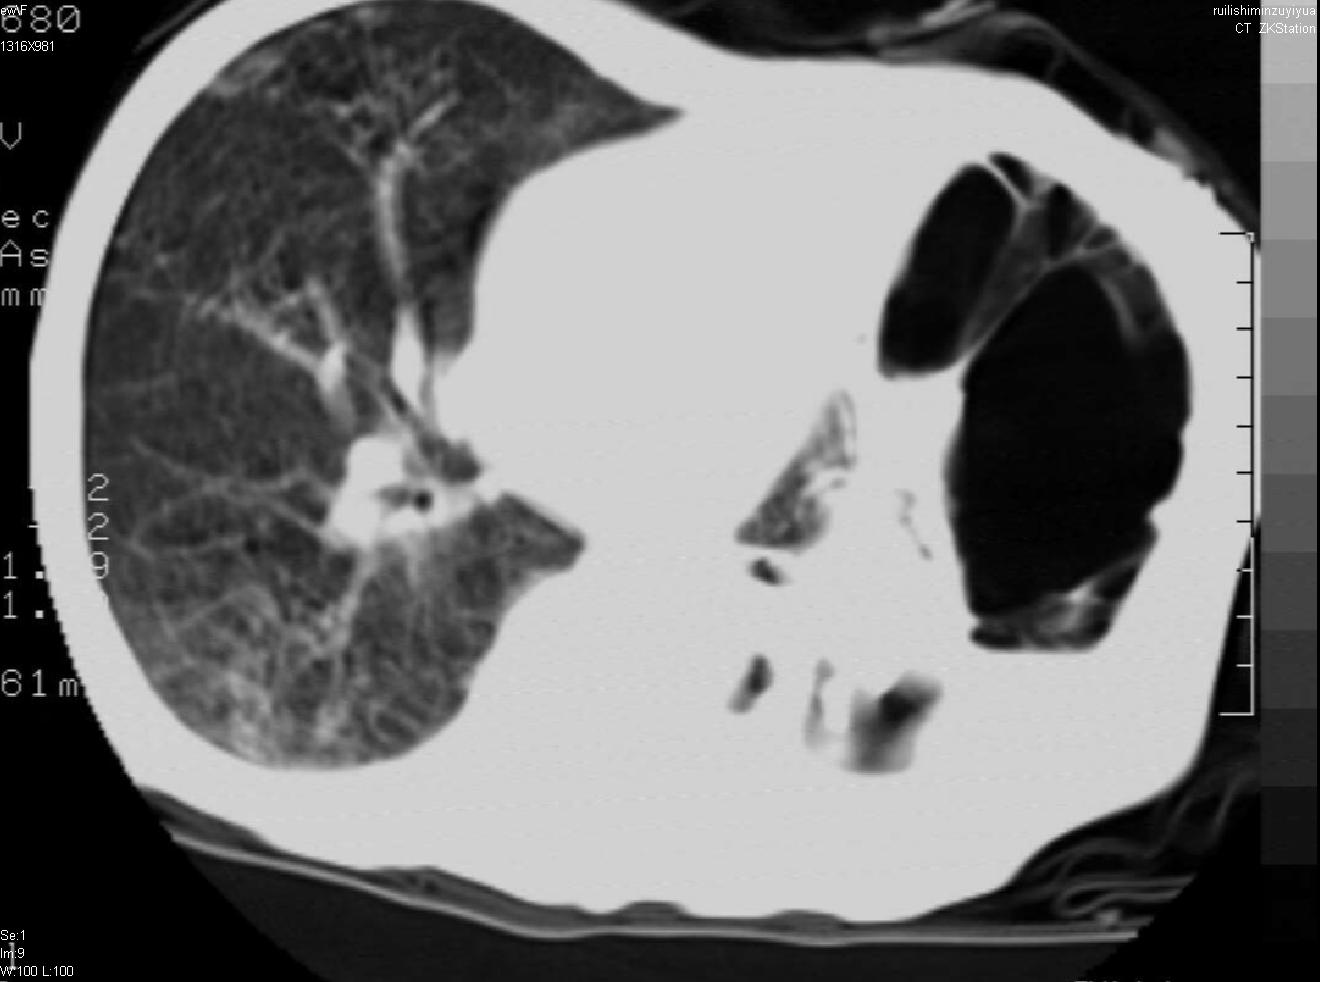

以下是引用天南地北在2007-6-11 23:32:00的发言:[br]1:左侧肺毁损(结核性)伴感染(多发空洞伴液平面)。[br]2:右肺继发型肺结核。

以下是引用avril在2007-6-12 1:17:00的发言:[br]1、左肺毁损。[br]2、左肺多发肺大泡伴自发性气液胸形成。[br]3、右肺继发型结核。

以下是引用尚峰在2007-6-11 22:44:00的发言:[br]慢阻肺、肺纤维化、肺大泡、气胸形成,此患者有没有急性病史?